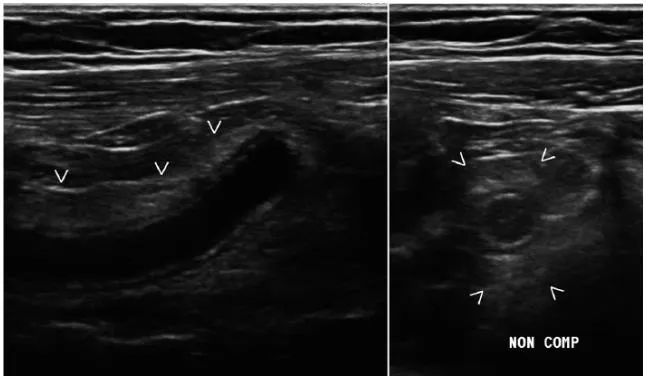

Lack of compressibility

96% 민감도와 특이도